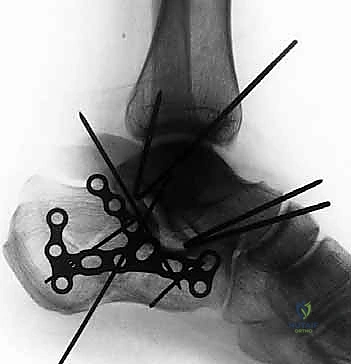

5. التثبيت النهائي باستخدام الشرائح والمسامير (Plating)

يتم وضع شريحة تيتانيوم (Titanium Plate) مصممة خصيصاً لتطابق الشكل التشريحي لعظم الكعب. يتم تثبيت هذه الشريحة بمسامير قوية لتوفير ثبات ميكانيكي صلب يسمح بالالتئام السليم ويمنع انهيار العظم مرة أخرى. في بعض الحالات التي يوجد فيها فراغ عظمي كبير، قد يستخدم الدكتور هطيف طعوماً عظمية (Bone Grafts) لملء الفراغ.

صور إضافية من داخل غرفة العمليات توضح دقة الإجراء

توضح الصور التالية مدى تعقيد الجراحة والدقة التي يتطلبها تثبيت عظم الكعب، والتي يعكسها التميز الجراحي للأستاذ الدكتور محمد هطيف: